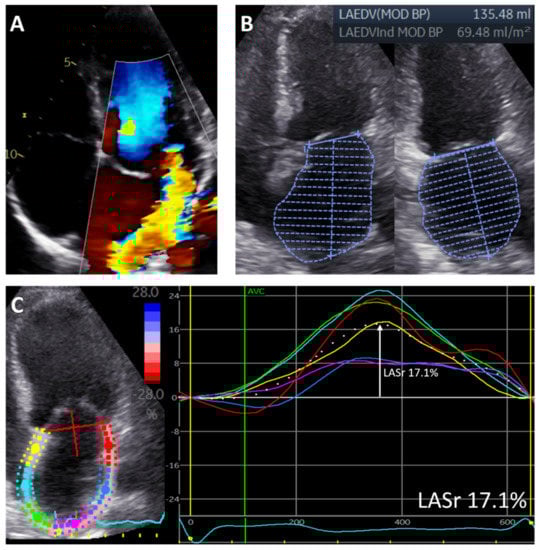

For the assessment of LA function, LA speckle-tracking strain was measured from the apical 4-chamber view with the onset of the QRS complex as the zero-reference point, according to current guidelines [19]. A region of interest was manually drawn along the LA endocardial border when LA was to its minimum volume after atrial contraction, excluding the pulmonary vein ostia and LA appendage. Automatic tracking of the LA wall by the software was visually verified and corrected by adjusting the region of interest or the width of the contour, ensuring appropriate capture of LA motion. LA reservoir strain (LASr) was then measured directly from the resulting LA strain versus time curve (Figure 1). To accurately assess the change in LA function over time, LASr was also adjusted for LAVi, since LA size changed significantly after MV surgery.

Figure 1. Measurements of left atrial volume and left atrial reservoir strain in a patient with significant primary mitral regurgitation. The figure shows a patient with significant primary MR (A) who had an enlarged LAVi (measured according to the biplane Simpson method) (B) and reduced LASr (measured as the peak value from the LA strain versus time curve derived from the 4-chamber view) (C). Regional strain curves are represented by different colors (yellow, red, blue, pink, green, light blue).